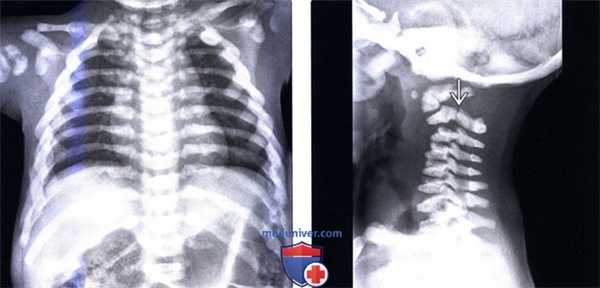

(Слева) На рентгенограмме грудного отдела позвоночника и грудной клетки в прямой проекции (инфантильный остеопетроз) определяется выраженное диффузное склерозирование всех костей. Обратите внимание на аномально утолщенные ребра и множественные консолидированные переломы ребер и ключиц.

(Справа) Рентгенограмма шейного отдела позвоночника в боковой проекции (инфантильный остеопетроз): выраженное склерозирование позвонков. Обратите внимание на перелом межсуставной части дуги С2 со смещением, связанный с патологической хрупкостью костей.